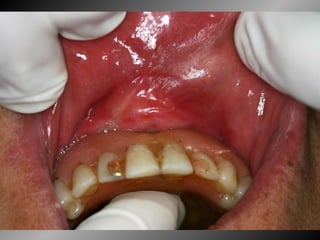

Granuloma Piogênico Lesão Nodular Séssil ou pediculada Avermelhada ou vinhosa Sangramento espontâneo e áreas de micro-ulceração superficial

Granuloma Piogênico Lesões nodulares de coloração avermelhada ou vinhosa Provavelmente uma reação inflamatória exagerada ao trauma menor Crescimento rápido, às vezes sangramento espontâneo Ocorre em qualquer idade mas parece mais freqüente em adultos jovens e adolescentes  Localização mais comum: gengiva (NEVILLE,2001)

Granuloma Piogênico Lesões mais antigas, são menos vasculares e mais fibrosas Papila interdental e regiões anteriores são áreas preferenciais, principalmente por vestibular (BORK,1996)

Granuloma Piogênico LesãoNodular Séssil ou pediculada Avermelhada ou vinhosa Sangramento espontâneo e áreas de micro-ulceração superficial

Granuloma Piogênico Lesõesnodulares de coloração avermelhada ou vinhosa Provavelmente uma reação inflamatória exagerada ao trauma menor Crescimento rápido, às vezes sangramento espontâneo Ocorre em qualquer idade mas parece mais freqüente em adultos jovens e adolescentes Localização mais comum: gengiva (NEVILLE,2001)

Granuloma Piogênico Lesõesmais antigas, são menos vasculares e mais fibrosas Papila interdental e regiões anteriores são áreas preferenciais, principalmente por vestibular (BORK,1996)